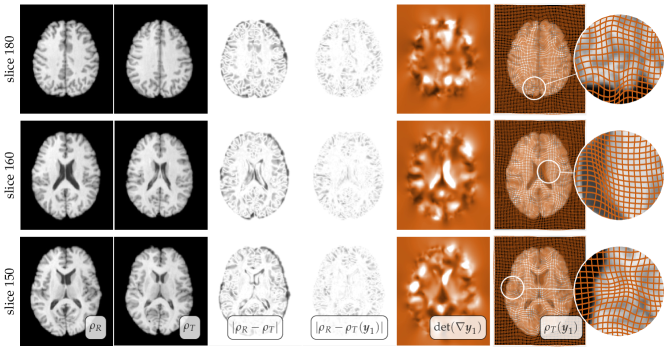

Refer to caption

Figure 1: The image registration problem (data taken from [50, 3]). The input (original data) are image intensities ρRsubscript𝜌𝑅\rho_{R} and ρTsubscript𝜌𝑇\rho_{T}. The output is 𝒚𝒚{\boldsymbol{y}}, the deformation map. Our goal is to find 𝒚𝒚{\boldsymbol{y}} so that ρT(𝒚)subscript𝜌𝑇𝒚\rho_{T}({\boldsymbol{y}}) (the deformed ρTsubscript𝜌𝑇\rho_{T}) is as close as possible to ρRsubscript𝜌𝑅\rho_{R} (with respect to some appropriate measure). One way to achieve this is to use rigid registration (i.e., searching for a map that entirely is described by rotations and translations). The result of a rigid registration is shown in the third image from the left; the fourth image shows the difference between the two images ρRsubscript𝜌𝑅\rho_{R} and ρTsubscript𝜌𝑇\rho_{T} after rigid registration. As one can see, there are still significant differences in the intensity values. If we use a deformable registration instead, we can compute a much more flexible 𝒚1subscript𝒚1{\boldsymbol{y}}_{1}, which results in a much smaller misfit |ρRρT(𝒚1)|subscript𝜌𝑅subscript𝜌𝑇subscript𝒚1|\rho_{R}-\rho_{T}({\boldsymbol{y}}_{1})|. The deformation map 𝒚1subscript𝒚1{\boldsymbol{y}}_{1} for this method is visualized in the last figure to the right. The grid lines, superimposed on top of ρT(𝒚1)subscript𝜌𝑇subscript𝒚1\rho_{T}({\boldsymbol{y}}_{1}) were a Cartesian grid before the deformation. We use them to visualize the overall deformation.